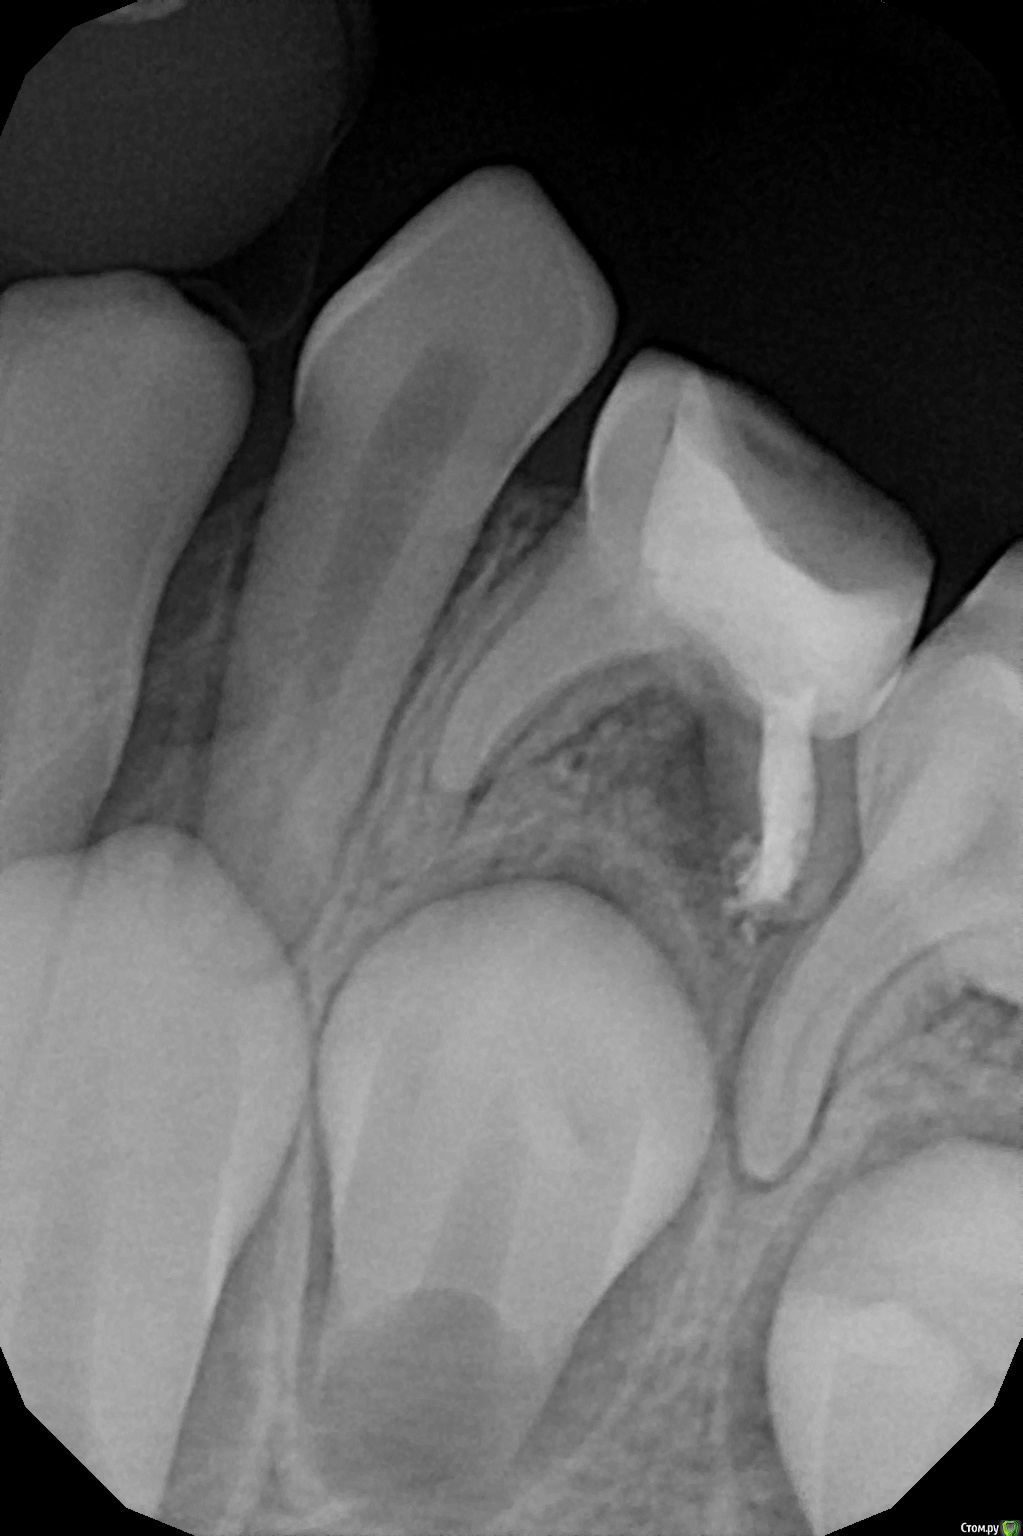

crown Опубликовано 9 декабря, 2016 Поделиться Опубликовано 9 декабря, 2016 О народ подтянулся, заодно и мой тогда посмотрите. 7 лет, 7.4, ранее резорциненный, в медиальных там все глухо, ток бором сверлить, в дистальном кальций оставил. Ссылка на комментарий

Джима Опубликовано 9 декабря, 2016 Поделиться Опубликовано 9 декабря, 2016 заживёт, постоит ещё немного. только метапекс из канала рассосётся очень быстро. Ссылка на комментарий

crown Опубликовано 9 декабря, 2016 Поделиться Опубликовано 9 декабря, 2016 заживёт, постоит ещё немного. только метапекс из канала рассосётся очень быстро.А если эодентом закатать? Ссылка на комментарий

Джима Опубликовано 10 декабря, 2016 Поделиться Опубликовано 10 декабря, 2016 быстротвердеющим низзя, обычным можно Ссылка на комментарий

crown Опубликовано 17 февраля, 2017 Поделиться Опубликовано 17 февраля, 2017 Кажись заживает, 2,5 месяца. Ссылка на комментарий

Brigita Опубликовано 17 февраля, 2017 Поделиться Опубликовано 17 февраля, 2017 Красавчики.И док и зуб))) 2 Ссылка на комментарий

Воркутов Опубликовано 13 мая, 2017 Поделиться Опубликовано 13 мая, 2017 Молодцы!!! Зуб спасен , ребенок доволен!! Ссылка на комментарий